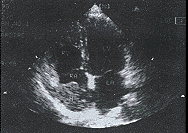

中国超声医学杂志990237 患者,男性,55岁,进行性消瘦,腹胀腹痛一月,加重伴双下肢肿胀一周来诊。体检:慢性消耗病容,精神差,皮肤巩膜黄染,双下肢肿胀,肝肋下4cm,腹部移动性浊音阳性。腹部B超及肝脏CT检查,均诊断为肝硬化合并肝癌、腹水。化验血AFP明显升高。临床诊断肝硬化合并肝癌无疑。患者既往无心脏病史,无双下肢肿胀史及下肢静脉炎。考虑患者近一周来双下肢肿胀尤为明显,且呈进行性加重,有下腔静脉受阻引起双下肢静脉回声障碍的可能,随行双下肢静脉、下腔静脉彩超检查及心脏超声心动图检查。超声结果:双下肢浅深静脉内径明显增宽,壁光滑,腔内未见异常回声。下腔静脉内径增宽,剑突下纵切,显示下腔静脉长轴及入右房切面,下腔静脉离右房入口4cm处,腔内见一不规则腊肠样不均匀中等实质性回声,不活动,与下腔静脉后壁关系紧密,长约7cm,最厚处约3cm,向上方伸入右房腔内(图1),呼吸时下腔静脉内径无变化。心尖四腔心切面,该肿物占右房容积的3/4(图2),右房轻度扩大。彩色多普勒:双下肢静脉、下腔静脉远端血流缓慢,入右房处下腔静脉内血流呈一条窄细的蓝彩血流束经下腔静脉前壁与该占位间的缝隙流入右房,三尖瓣口见少量返流。彩超诊断:右房、下腔静脉内巨大癌栓(肝癌转移)。因属肝癌晚期,行手术取栓已无意义,患者放弃治疗出院。

右房内巨大癌栓

图2 心尖四腔心